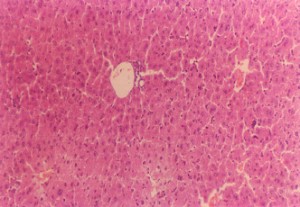

垂盆草エキス中容量+四塩化炭素により損傷を受けたマウス肝臓(200×)